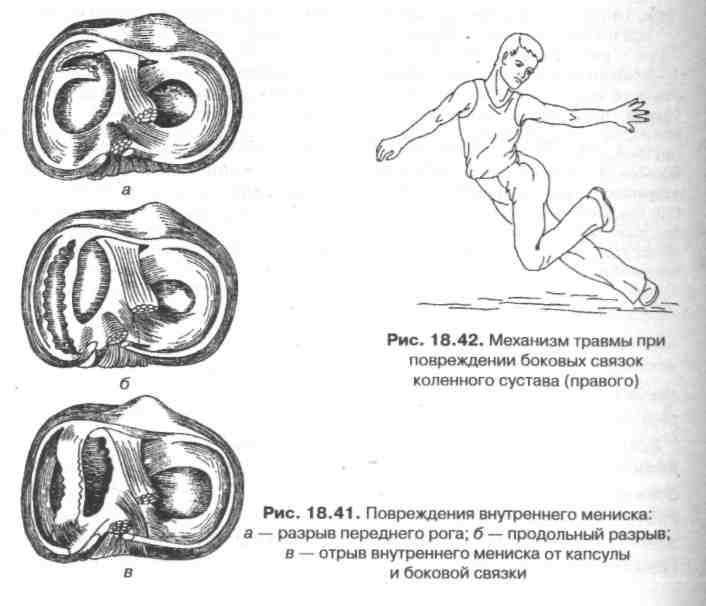

Причины и лечение травм коленного сустава